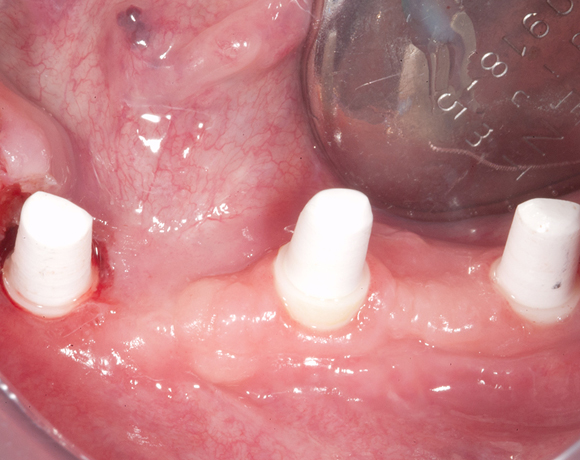

Knochenspaltung Unterkiefer 32 – 36

Die Knochenspaltung auch Bonesplitting genannt, ist eine geeignete Möglichkeit im Unterkieferseitenzahnbereich Knochen aufzubauen, um Implanate setzen zu können. Vorraussetzung ist eine ausreichende Knochenhöhe.

Bei diesem Patientenfall war vor dreizehn Jahren bereits eine Knochenspaltung besprochen

worden, die Patientin hatte allerdings Angst vor dem Eingriff und sich für eine herausnehmbare

Lösung entschieden. Nachdem die endodontisch behandelten Zähne 32 und 33, die mit VMK – Kronen

und Geschiebe versorgt waren, abgebrochen sind, war die Patientin für den Eingriff mit Knochen-

spaltung und drei Implantaten offen. Heute ist sie sehr zufrieden und bereut es nicht gleich diese

Lösung gewählt zu haben.